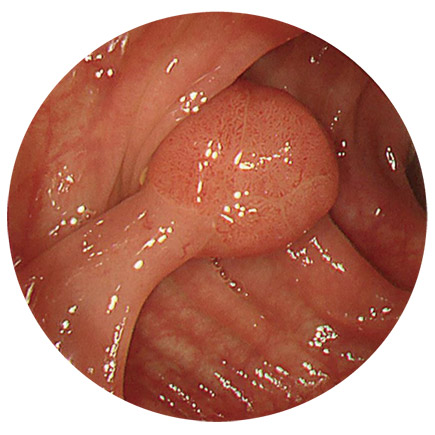

大腸ポリープ

(がんの芽のようなもの)

大腸がんのでき始めは、一般的にはポリープ(おでき、いぼのようなもの)の形をしており、当院では、大腸カメラを行ったその場で検査と同時に切除することができます。

内視鏡でポリープを切除する目的は、先々大腸がんに育つ前に「がんの芽を摘む」ことです。